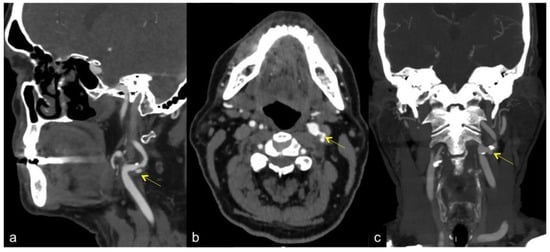

3. Computed Tomography Angiography (CTA) and Magnetic Resonance Angiography (MRA)

- Dong, Z.; Zhou, C.S.; Li, H.X.; Shi, J.Q.; Liu, J.; Liu, Q.; Su, X.; Zhang, F.; Cheng, X.; Lu, G. Radiomics versus conventional assessment to identify symptomatic participants at carotid comupted tomography angiography. Cerebrovasc. Dis. 2022, 51, 647–654. [Google Scholar] [CrossRef] [PubMed]